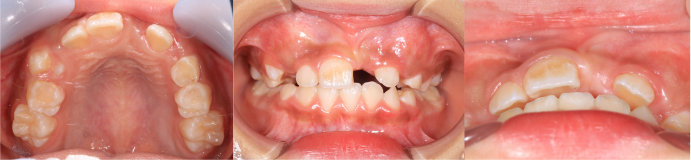

| Case4 |

| 前歯のガタガタ |

| <治療前> |

| <治療後> |

| 主訴 |

上の前歯がガタガタしている |

| 診断名 |

上顎前歯の重度の叢生、下顎前歯の中程度の叢生 |

| 年齢 |

8歳 |

| 使用装置 |

マルチブラケット装置 |

| 抜歯部位 |

永久歯の抜歯は無し |

| 治療期間 |

3年9か月 |

| 治療費概算 |

検査・診断料:5万円+税 装置・技術料:25万円+税 おおよそ1か月ごとの処置・管理料:5,000円+税 保定装置料:5万円+税 |

| リスク・副作用 |

う蝕 |